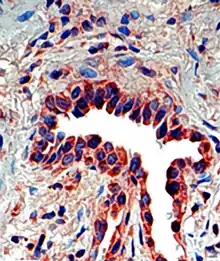

Osteopontin seen in a lung tissue sample from a patient with ideopathic pulmonary fibrosis.

Osteopontin is expressed in a variety of tissue types including cardiac fibroblasts,[25] preosteoblasts, osteoblasts, osteocytes, odontoblasts, some bone marrow cells, hypertrophic chondrocytes, dendritic cells, macrophages,[26] smooth muscle,[27] skeletal muscle myoblasts,[28] endothelial cells, and extraosseous (non-bone) cells in the inner ear, brain, kidney, deciduum, and placenta. Synthesis of osteopontin is stimulated by calcitriol (1,25-dihydroxy-vitamin D3).